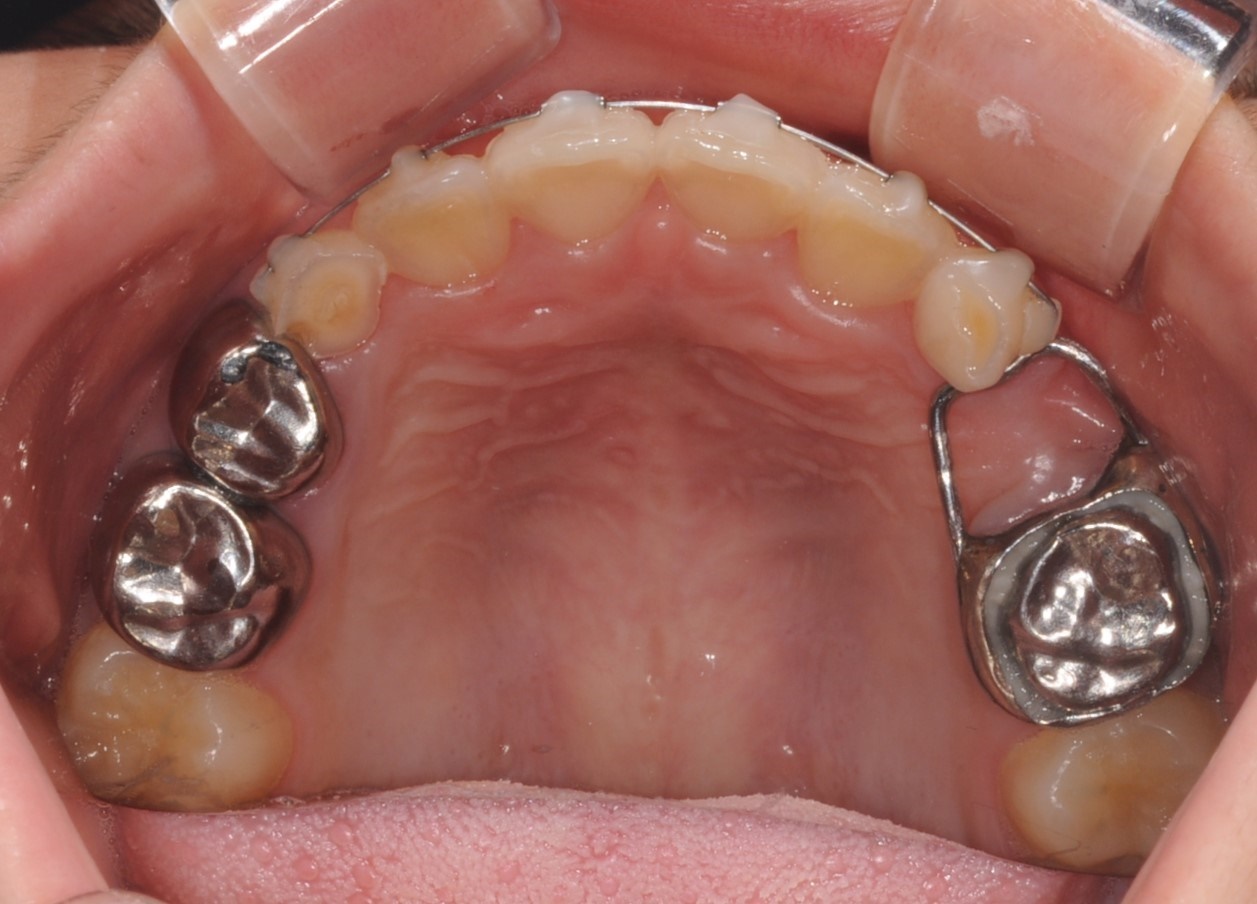

NHA

(Nance holding Appliance)

상악에서 유치의 조기발거 시,

영구치 맹출시기까지 공간을 유지합니다.

상악 공간을 유지하며,

맹출 공간 부족을 방지 및

어금니의 솟음을 방지합니다.